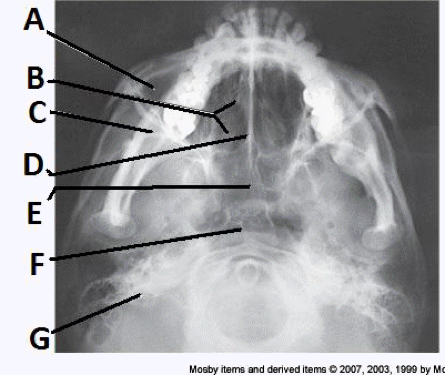

____ 13. Examine the image of the paranasal sinuses below. The letter A labels the:

a. sphenoid sinuses

b. frontal sinuses

c. ethmoid sinuses

d. maxillary sinuses

bb. frontal sinuses

____ 32. Examine the image of the paranasal sinuses below. The letter A labels the:

c. crista galli

d. ethmoid sinuses

____ 37. Examine the image of the paranasal sinuses below. The letter F labels the:

a. maxillary sinuses

b. sphenoid sinuses

d. pharynx

dd. pharynx

____ 61. Examine the image of the paranasal sinuses below. The letter C labels the:

a. petrous ridge

b. vomer

c. sphenoid sinuses

d. condyle of the mandible

aa. petrous ridge

____ 136. Examine the image of the paranasal sinuses below. The letter B labels the:

a. frontal sinuses

b. maxillary sinuses

d. sphenoid sinuses

cc. ethmoid sinuses

____ 174. Examine the image of the paranasal sinuses below. The letter E labels the:

b. ethmoid sinuses

c. frontal sinuses

aa. sphenoid sinuses

____ 184. Examine the image of the paranasal sinuses below. The letter B labels the:

aa. maxillary sinuses

____ 191. Examine the image of the paranasal sinuses below. The letter C labels the:

a. ethmoid sinuses

c. petrous ridge

bb. maxillary sinuses